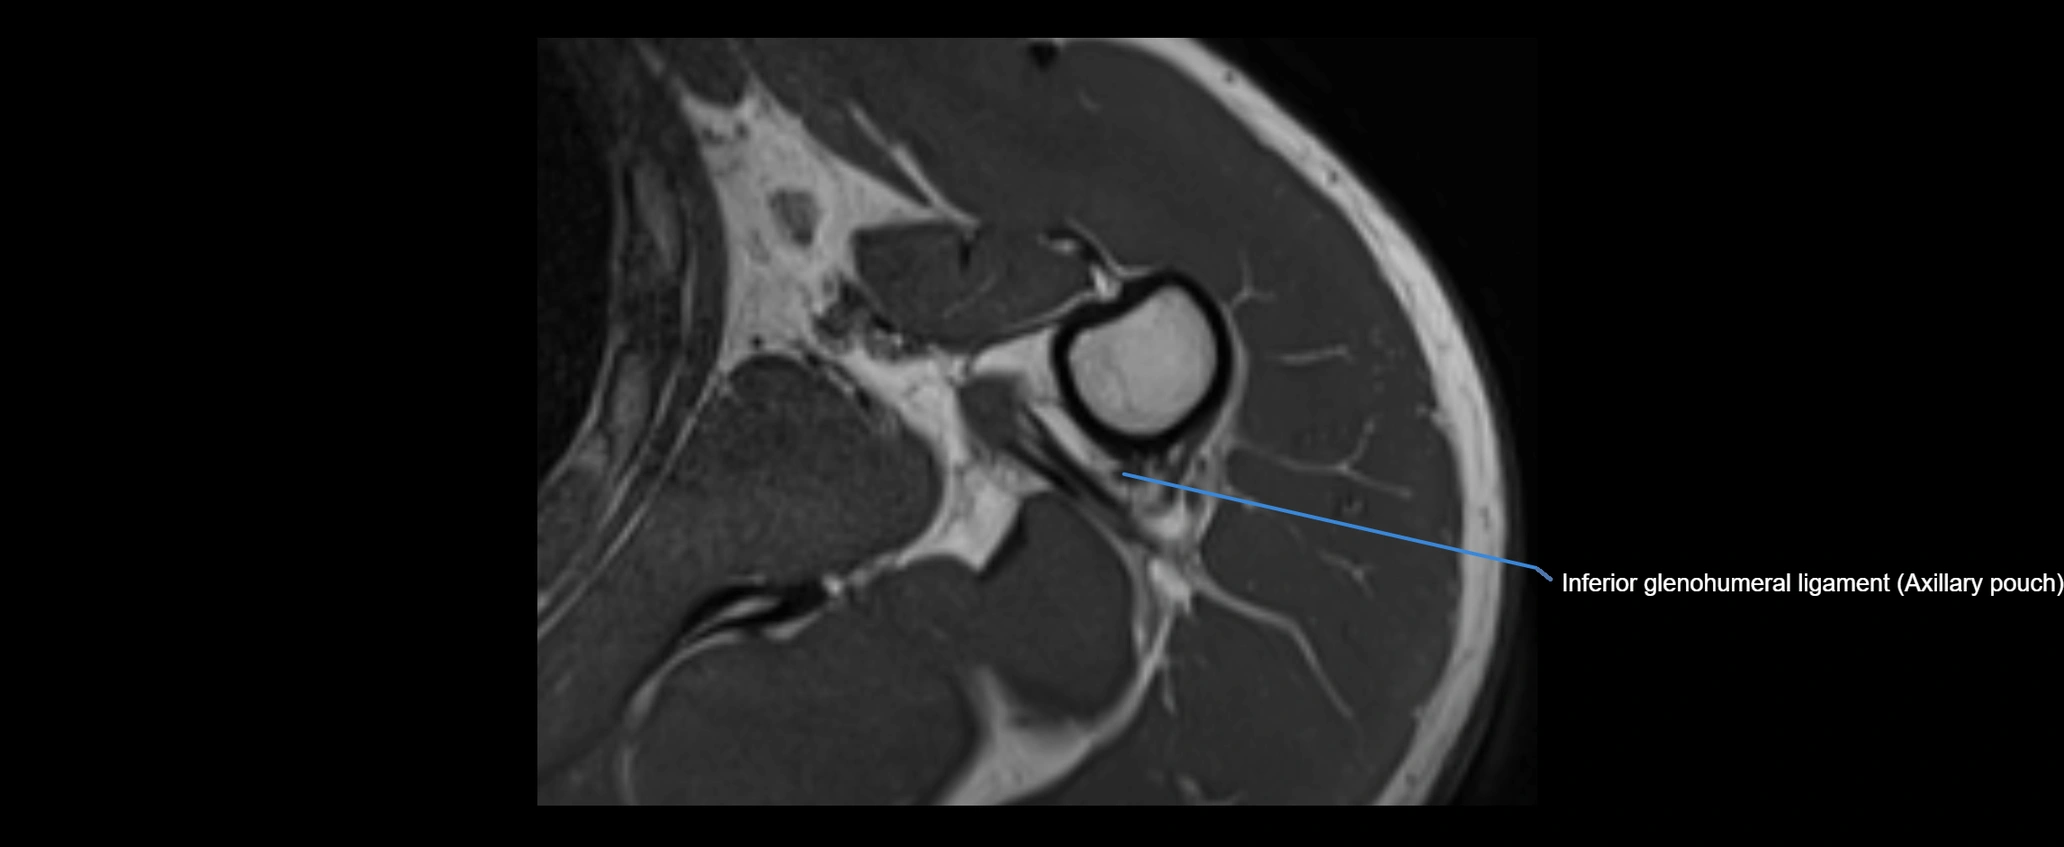

CT image

image